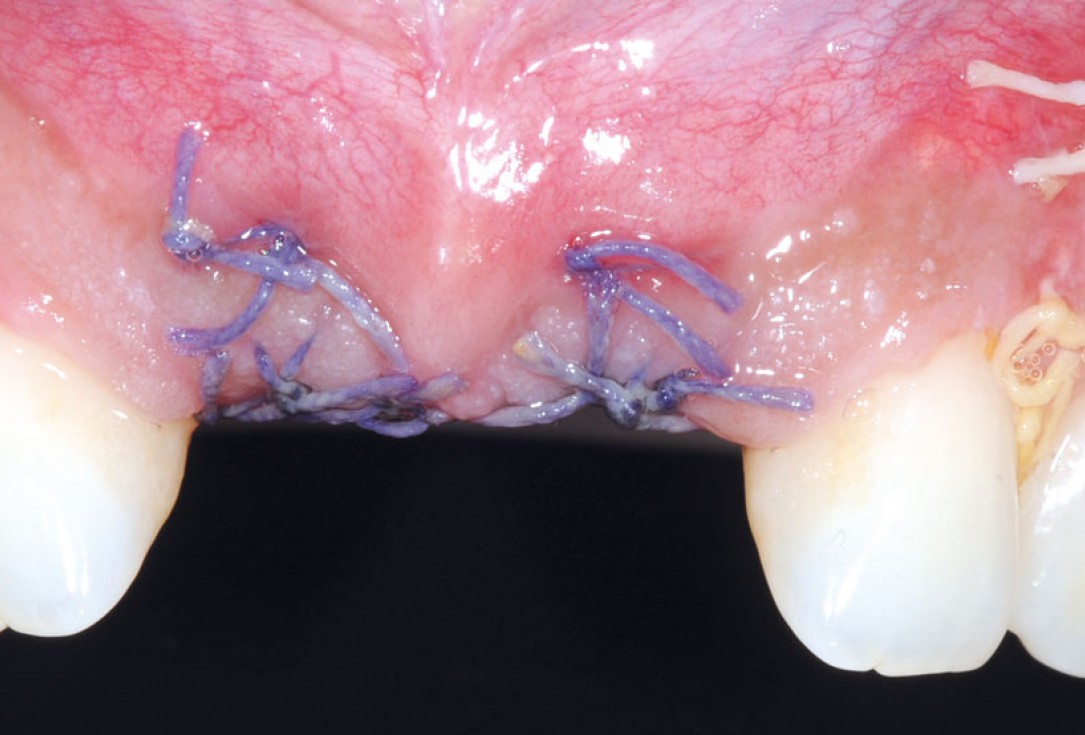

18/26 - Sutured free of tension with vycrilBone augmentation in aesthetic zone with maxgraft® bonering - Dr. A. Patel